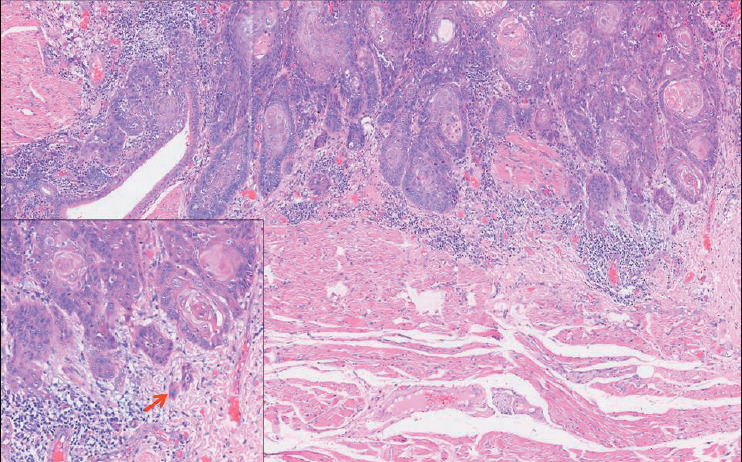

目的:口腔鳞状细胞癌是世界上最常见的头颈部恶性肿瘤。肿瘤出芽是一种组织病理学特征,其特征是在侵袭性肿瘤前部的基质中分散存在孤立的单个/小簇癌细胞。在印度,其在唇部和口腔鳞状细胞癌中的预后意义尚未得到太多研究。本研究的目的是在印度北喀拉拉邦的一个三级癌症中心对333例口腔鳞状细胞癌患者进行大型单中心回顾性队列研究,探讨肿瘤出芽在预后中的作用。材料与方法:从病理档案中检索2018 - 2020年333例口腔鳞状细胞癌的初切切片,由2名独立病理学家对肿瘤出芽及其他组织病理参数进行评估。生存数据从患者档案中收集。结果:我们使用卡方分析发现肿瘤出芽与其他已知的组织病理学预后因子之间存在显著关联。单因素logistic分析显示,肿瘤出芽、浸润深度(bbb10 mm)、最坏浸润方式5和神经周围浸润与局部复发/远处转移显著相关。多因素logistic回归分析发现肿瘤出芽是局部复发/远处转移的独立预后指标。单因素cox比例分析显示,口腔鳞状细胞癌患者的肿瘤出芽、浸润深度(bbb10 mm)、最坏浸润方式5、病理T4分期和神经周围浸润与总生存期降低和无病生存期差相关。多变量cox比例分析显示,肿瘤出芽是总生存期下降和无病生存期差的唯一独立预测因子。结论:基于本研究,我们可以得出结论,肿瘤出芽是一个简单可靠的独立预后指标,有助于口腔鳞状细胞癌患者的个性化治疗。

Objective: Oral squamous cell carcinoma is the most common head and neck malignancy reported worldwide. Tumor budding represents a histopathological feature characterized by the presence of isolated single/small clusters of cancer cells dispersed within the stroma at the invasive tumor front. Its prognostic significance has not been studied much in lip and oral squamous cell carcinomas in India. The aim of this study was to investigate the prognostic role of tumor budding in a large single-center retrospective cohort of 333 patients with oral squamous cell carcinoma at a tertiary cancer center in North Kerala, India.